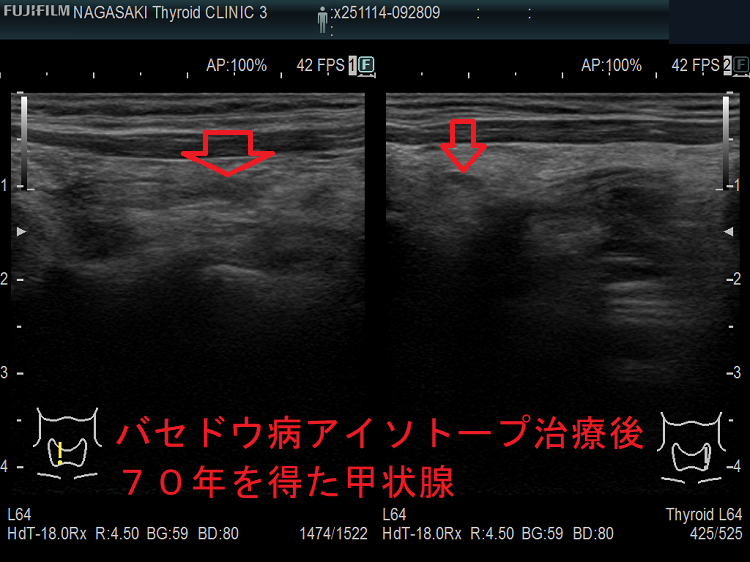

数年で放射線治療後甲状腺機能低下症になり、甲状腺ホルモン剤[チラーヂンS錠(レボチロキシン ナトリウム)]の服薬が生涯必要になります。しかし、

新たに提唱された「甲状腺機能正常を目指した治療目標」のため、中途半端な量あるいは少量のアイソトープ(放射性ヨウ素; I-131)を使用した場合、甲状腺機能亢進症が再発するのは当然と思います(新しく提唱された治療目標)。筆者に言わせれば、甲状腺機能亢進症/バセドウ病を甘く見過ぎています。

一方、アイソトープ(放射性ヨウ素; I-131)治療が成功して、甲状腺重量が10g以下に十分縮小し、甲状腺ホルモン補充療法が必要となった後でも、稀に甲状腺中毒症状態になる場合があります。

ましてや、中途半端に甲状腺組織が残存していれば、そのリスクはさらに高くなります。